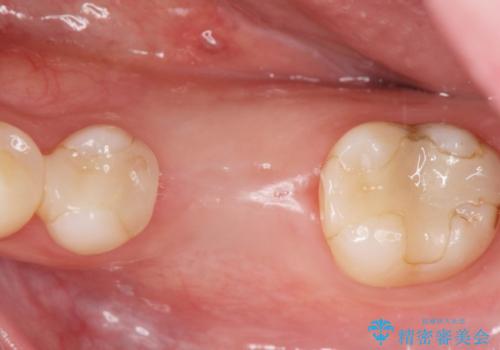

欠損部のインプラント補綴

- 失った奥歯にインプラント治療を受けたい、と希望され来院されました。

前後の歯を削らずに機能回復できるインプラントを用いて審美生、咬合機能の回復を計画します。

痛みや腫れもほとんどなくインプラント治療を終えられ、しっかり噛むことができるようになった。と治療結果に満足いただくことができました。